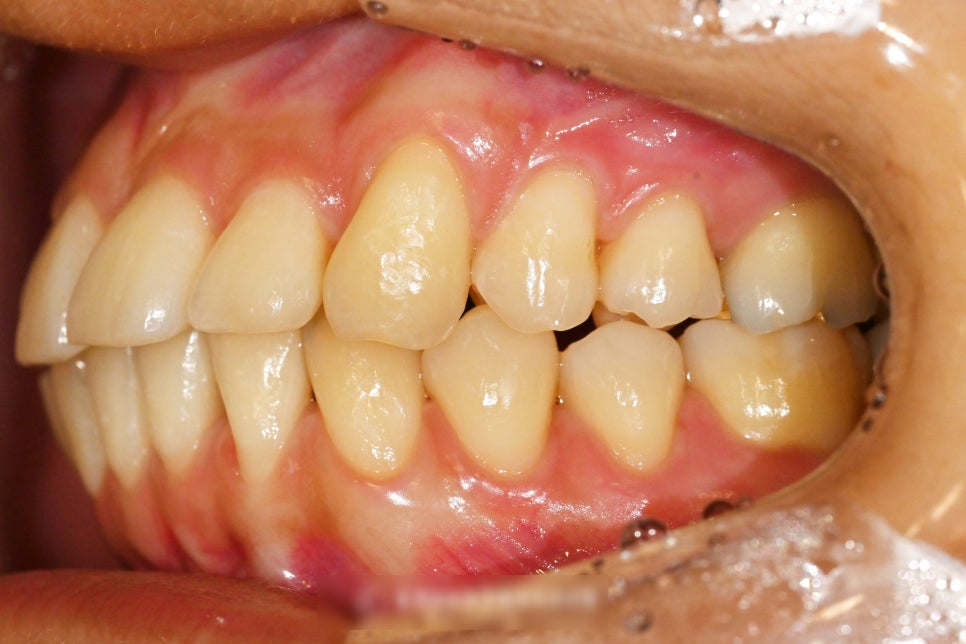

이어서 구강 내 사진을 보여드립니다.

우선 하악부터 살펴보면

가운데 중심을 기준으로 하여

오른쪽 송곳니 부분으로 중심이

쏠려있다는 양상을 보여줍니다.

이전에 붙여둔 유지 장치 retainer를

붙여둔 안쪽이 훤히 다 드러날 정도로

무언가 배열이 틀어졌음을 알 수 있습니다.

위쪽에서는 큰 특이사항은 없어 보이나

위아래 맞물리는 관계에서 보았을 때는

이로 인해 고쳐야 될 부분들이 발견 됩니다.

오른쪽 아래 43번 송곳니를 기준으로

맞닿는 위쪽과의 관계를 보면

앞니 교합이 떠있는 것이 확인 됩니다.

이렇게 맞지 않는 앞니 교합을 가질 경우에는

추후 생길 수 있는 네거티브들이 많습니다.

특정한 치아에 교합력이 몰리게 되며,

이에 따라서 특정 치아의 수명이

급격히 짧아지는 부작용을

초래할 수 있습니다.

조금 더 나아가 TMJ(턱관절)에도

부정적 영향을 줄 가능성이 있습니다.